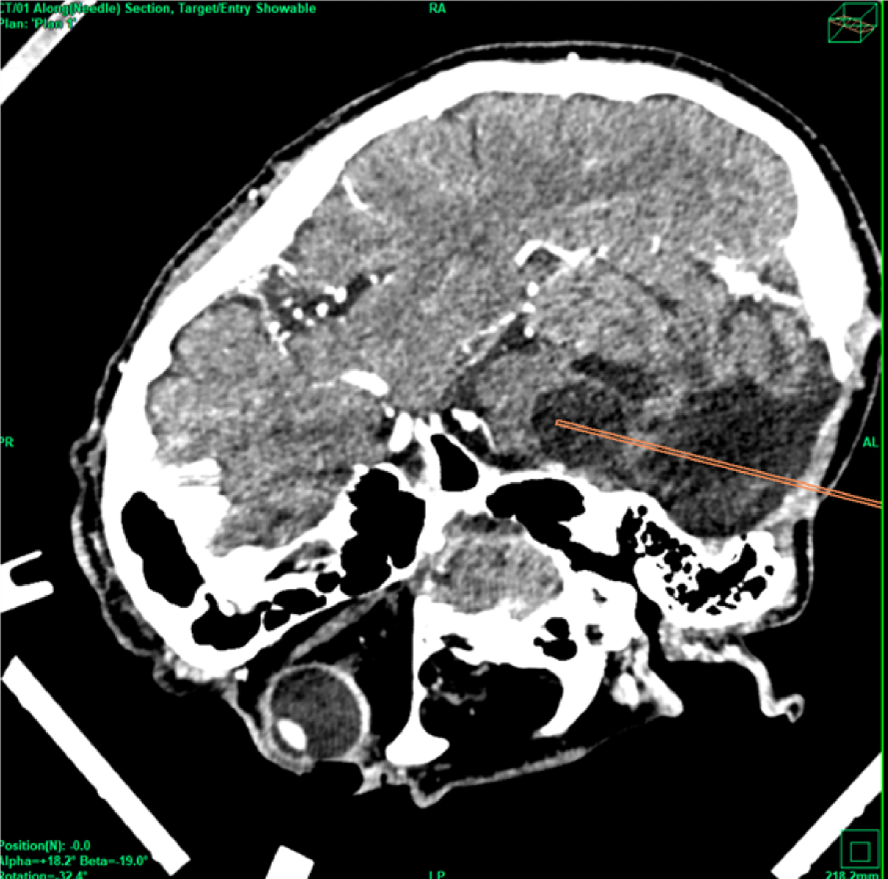

The patient was offered the alternative treatment of open fenestration and was informed that there was little to no experience regarding the outcome of this new procedure. Informed consent was obtained. On the day of the procedure, the patients received total intravenous anesthesia and a single shot of 1.5 g cefuroxime. The patient’s head was fixed in a aluminum ring (Precisis AG, Heidelberg, Germany) within a prone position. MR images with 2mm slices and a stereotactic CT were uploaded into the inomed iPS 6.0 software (inomed, Emmendingen, Germany). Several potential trajectories were evaluated to determine the safest surgical approach. A parietal transtentorial route was ultimately selected (Figure 4).

Figure 4 Stereotactic parietal transtentorial approach within the stereotactic CT scan (top) and within the MRI (bottom).